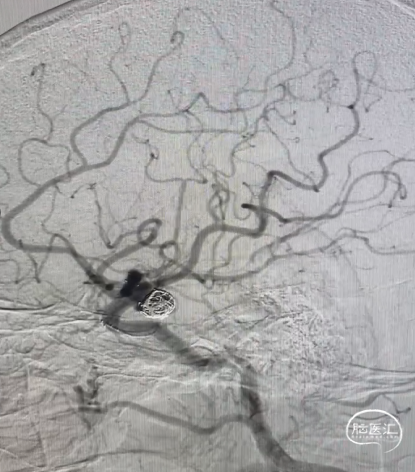

手术过程

Synchro14微导丝牵引支架微导管到位;弹簧圈微导管到位。

送入3*6mm弹簧圈成篮,同时摆一根支架微导管在上干,为T型支架做准备;

释放一枚Leo baby支架 2.5*25mm。

因下干支与M1成角太锐,支架在转弯处打开,多次推拉调整,以“神龙摆尾”方式释放,将支架尾端避开上干开口。

释放支架后,再依次送入2*3mm、1.5*2mm两枚弹簧圈完成治疗。

术后造影显示各分支血管通畅,动脉瘤不再显影。